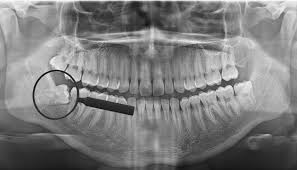

Wisdom teeth, also known as third molars, often become impacted or grow at angles that can cause pain, infection, or damage to adjacent teeth. Removal is typically recommended when there isn't enough space in the jaw for them to erupt properly or when they are causing clinical complications.

Wisdom teeth X-ray Wisdom tooth extraction procedure